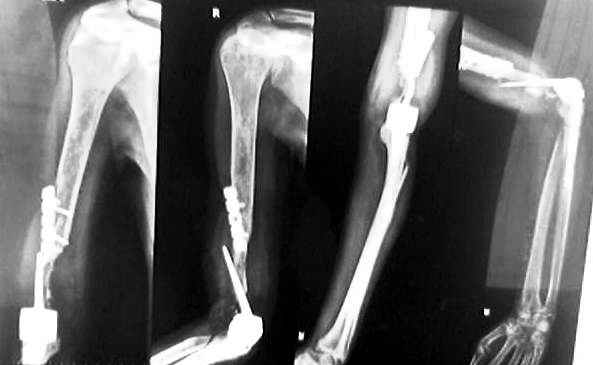

Мужчине 23 лет 3 года назад выполнен остеосинтез плеча, потерял движения в локтевом суставе. 1 год назад - эндопротезирование локтевого сустава,

инфекция, кожная пластика, попытка закрыть дефекттканей лоскутом на ножке безуспешна.Сейчас - инфицированный имплантат обнажен, нет функции лучевого и срединного нервов, движений в локтевом суставе нет.Что делать дальше?PATIENT HAS BEEN REFERRED TO ME WITH THE FOLLOWING HISTORY23/M , H/O # RIGHT ELBOW JT 3YRS, ORIF DONE WITH 4.5 RECONSTRUCTION PLATE, NO ROM AT ELBOW,2ND STAGE T.E.R DONE,1 YEAR,INFECTION SKIN GRAFTING & FLAP ATTEMPTED BUT FAILEDO/E :FRANK INFECTION IMPLANT EXPOSED, RADIAL & MEDIAN NERVE PALSY ROM AT ELBOW JOINT 0 DEGREESHOW DO WE GO ABOUT WITH IT FROM HEREDR.R.M.WADERAORTHOPAEDIC SURGEON MUMBAI